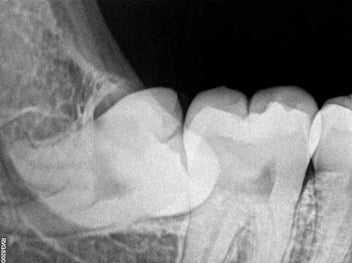

An abscessed tooth occurs when a bacterial infection creates a pocket of pus within the tooth or surrounding gum tissue. This infection typically starts from untreated tooth decay, a cracked tooth, or gum disease. The infection can spread to the surrounding tissues and even to other parts of the body, making it a serious health concern.

- Drainage: The dentist may need to drain the abscess to remove the pus and reduce pressure. This can be done by making a small incision in the gum or through the tooth itself.

- Root Canal Treatment: If the tooth can be saved, a root canal treatment may be performed. This involves removing the infected pulp, cleaning the root canals, and sealing them to prevent further infection.

- Tooth Extraction: In cases where the tooth is severely damaged and cannot be saved, it may need to be extracted to prevent the infection from spreading.